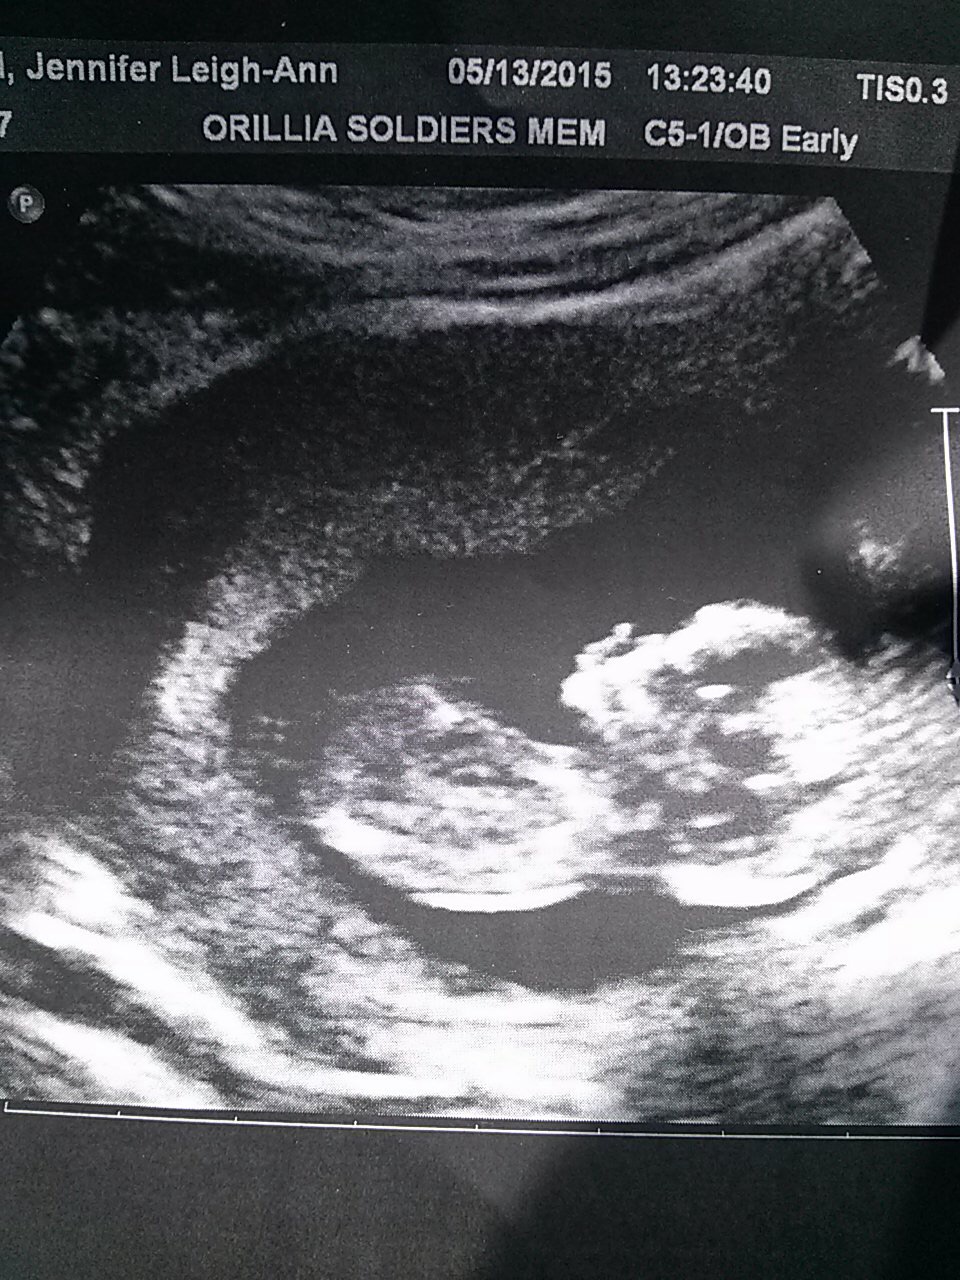

Show me those ultrasound pics!